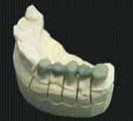

Üstte: Dişleri ve çene kemiği arızaları konusunda ameliyat planlaması için tomografi verisine bağlı olarak inşa edilen çene kemiği ve diş modelleri: Sağdaki modelde, dişler rahat görünebilmesi için ayrı bir renk ile imal edilmişlerdir. Bu gibi modeller ameliyatı planlamakla sorumlu doktorlar için çok yararlı olmaktadır. Böyle renkli modellerin imalatı için, emilen lazer enerjisine bağlı olarak rengini değiştiren Stereocol isimi özel bir fotopolimer reçine kullanılmaktadır. İmalat sonrası güneş ışığındaki UV sebebiyle tüm modelin renk değiştirmesini önlemek için model yüzeyi UV bariyer görevi yapan ve steril de edilebilen özel bir vernikle kaplanır.

Sağda: EOS firması'nın otoinşa cihazı ile imal edilmiş bir çene kemiği modeli.

Resmin sağında, EOS'un geliştirdiği özel destek yapısı gözükmektedir.